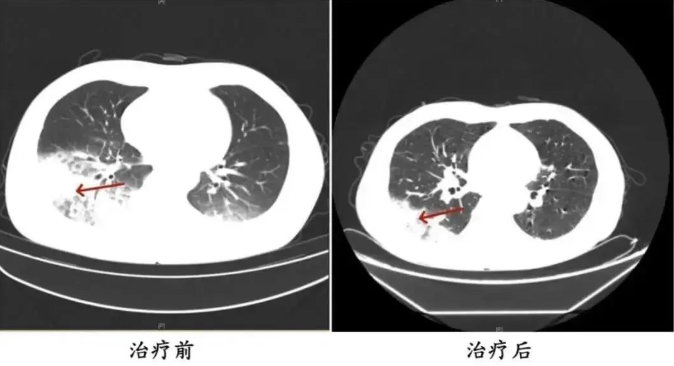

55岁的长沙市民周先生(化名),近日因持续发热、寒战、咳嗽4天在医院就诊后住院接受治疗询问病史得知,患者入院前启动了久未清洗的车载空调,每天在车上的时间超过10小时

经诊断,患者感染了军团菌肺炎

与周先生同一时间入院的,还有32岁的姚女士(化名)

据她介绍,家中的空调已有半年多未曾清洗

入院前她在家使用了两天空调

一周后相继出现了:咳嗽、咳痰、高热、寒战及呕吐、腹泻等症状

最终被确诊为重症军团菌肺炎